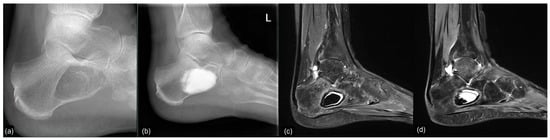

Figure 10.

Conventional radiological and MR tomographic follow-up of case 23: (a) preop, (b) 3 days postop, (c) 8 weeks postop, and (d) 3.5 months postop. Leakage of Cerament© was observed clinically (“white-out”) and radiologically.